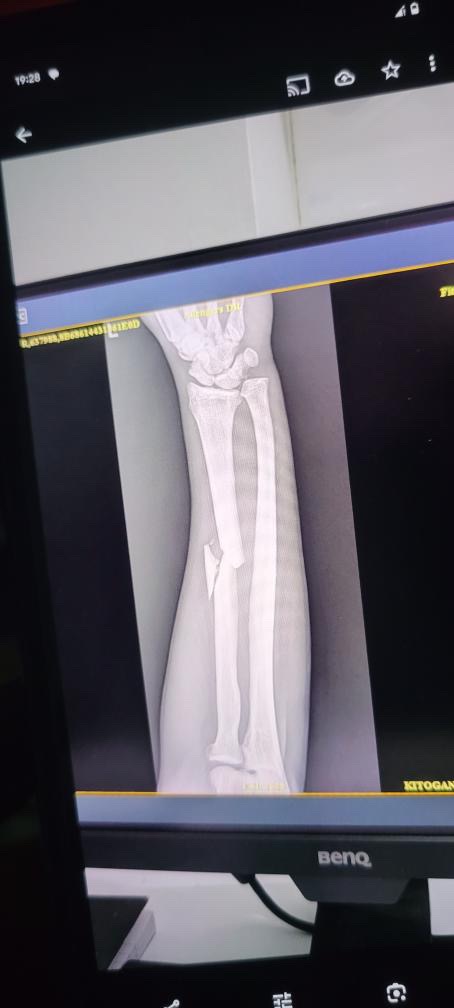

Unglücklicherweise hatte er vor ein paar Tagen einen schweren Motorradunfall und hat dabei einen komplizierten Bruch am linken Arm erlitten.

Omari braucht dringend eine Operation, um sich zu erholen und seinen Arm wieder vollständig benutzen zu können. Ohne diesen Eingriff wird es für ihn sehr schwer, zu arbeiten und seinen Lebensunterhalt zu verdienen – seine Kunst ist nicht nur seine Leidenschaft, sondern auch seine Existenzgrundlage.